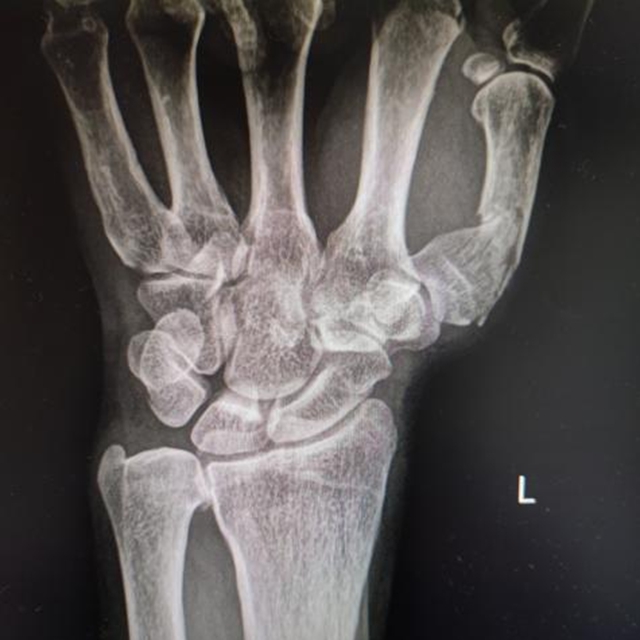

出院1年半后患者功能恢复情况

复位前

复位固定后